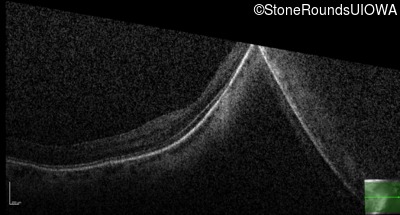

Age at visit: 41 years (Visit 2)

OD OS

This 41 year old woman was highly myopic as a child and experienced a rhegmatogenous retinal detachment OS at age 20.

Refraction OD:     -17.25 +1.00 x 93

Refraction OS:     -18.25 +3.50 x 56

The clinical features favoring the diagnosis of Sticker syndrome in this patient include extensive radial lattice degeneration, a personal and family history of rhegmatogenous retinal detachment, a history of cataract surgery before age 30 (and very high myopia before that), arthritis in her knees and hips and a slightly flattened mid-face.